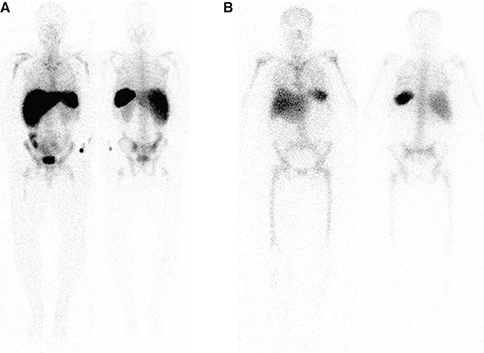

This radiopharmaceutical requires the patient’s own blood for labeling of autologous leukocytes. Following labeling, care must be taken to ensure that the same patient receives its own labeled leukocytes. This can be a challenge, especially if more than one patient is being evaluated with labeled leukocytes on the same day. The mechanism of localization is direct visualization of the infectious process due to accumulation of radiolabeled leukocytes. 111In has a 67-hour half-life, is cyclotron produced, and decays via electron capture. The photopeaks are 173 keV and 247 keV. Patients need to have adequate blood counts for appropriate labeling, with a minimum of 4,000 white blood cells. To label the leukocytes, about 20 mL of blood is withdrawn and is usually sent to a central radiopharmacy for radiolabeling, then returned the same day for injection. The normal biodistribution of 111In-oxine -labeled leukocytes is shown in Figure 2. Importantly, 111In-oxine labeled leukocytes do not have normal activity in the urinary tract or gastrointestinal tract, so if infection is suspected in the abdomen, this would be the labeled leukocyte of choice (2). Labeled leukocytes can also be used in applications such as the diabetic foot and Charcot joint to evaluate infection, along with additional or potentially concomitant dual isotope imaging (if performed with 111In-oxine labeled leukocytes) with 99mTc-sulfur colloid bone marrow imaging. This has a sensitivity and specificity rivaling that of magnetic resonance imaging (MRI). MRI often is difficult to interpret in the setting of diabetic foot and Charcot joint infections. Labeled leukocytes are poor at detecting vertebral osteomyelitis (3) and somewhat less poor at detecting etiologies of fever of unknown origin (46). FDG PET/CT outperforms in this setting.

Fig 2

Figure 2 Normal biodistribution of radiolabeled leukocytes. A. 99mTc-HMPAO labeled leukocytes, and B. 111In-oxine labeled leukocytes. Note the lack of GI tract and urinary tract activity on the 111In-oxine labeled leukocytes.

99mTc-HMPAO-LABELED LEUKOCYTES

This radiopharmaceutical also requires the patient’s own blood for labeling of autologous leukocytes with similar requirements for number of leukocytes and labeling process as 111In-Oxine labeled leukocytes. Similar care with delivery of the labeled leukocytes to the correct patient should be employed. 99mTc has a half-life of 6 hours and a photopeak of 140 keV, decaying by isomeric transition (7). 99mTc-HMPAO-labeled leukocytes will have normal activity in the bowel and urinary tract. Normal biodistribution is shown in Figure 2.